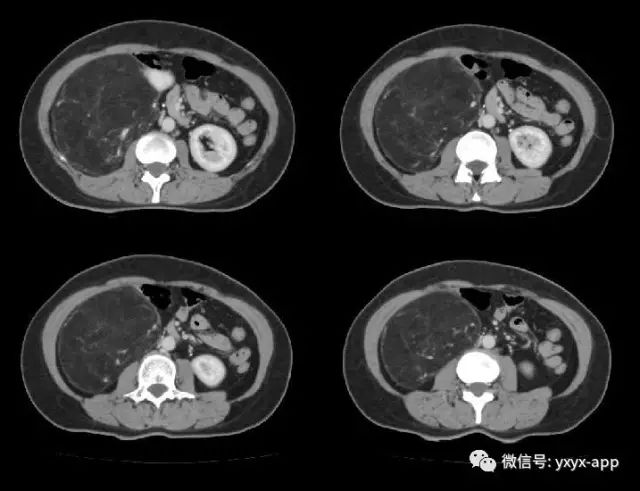

肚肚丫头:右肾中极肾皮质欠完整,呈喇叭口样改变,并可见突出肾脏轮廓的巨大脂肪密度影,其内信号欠均匀,病变边界清楚,周围脏器未见异常密度影及受侵征象,增强扫描病变呈欠均匀较显著强化,腹膜后未见肿大淋巴结。考虑来源于肾脏的含脂肿瘤占位病变,右肾巨大血管平滑肌脂肪瘤可能。鉴别诊断:1. 肾周脂肪肉瘤;2. 腹膜后脂肪瘤/高分化脂肪肉瘤;3. 肾上腺髓质脂肪瘤; 4. 腹膜后畸胎瘤。

【病理结果】肾脏血管平滑肌脂肪瘤

血管平滑肌脂肪瘤是肾脏最常见的良性肿瘤,病理上由平滑肌、脂肪细胞和异常血管混合组成,它们的含量差别较大,多数以脂肪成分为主,少数以平滑肌为主。好发于中年女性,大多数为单侧单发,少数为双侧多发。临床表现主要有肾区疼痛,可有血尿及腹部包块,少数临床上无任何不适症状,体检时偶然发现。

CT 诊断主要根据肿瘤内脂肪成分的显示以及肿瘤内粗大的血管影,由于肾血管平滑肌脂肪瘤含脂肪组织,CT 值在-10~-120HU,增强扫描肿瘤内血管平滑肌组织可明显强化,脂肪组织无强化。由于瘤内血管明显扩张、增厚,缺乏弹力内膜,故常发生肿瘤出血或肾包膜下出血。脂肪成分小于20%的血管平滑肌脂肪瘤影像难以显示脂肪,缺乏特异性的影像表现,不易作出定性诊断,与早期肾癌鉴别困难。